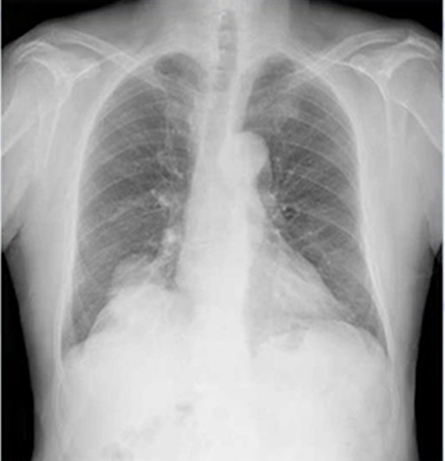

肺癌のレントゲン(X-p)写真②

肺癌の特徴として下記のものがあることを説明しました。

結節影(けっせつえい):

本来、空気を含んで黒く映るはずの肺に、直径3cm以下の円形や楕円形の白い影として現れます。これは肺の組織ではない「しこり(腫瘤)」の可能性があることを示します。

浸潤陰影(しんじゅんいんえい):

炎症などにより肺に水分が溜まり、境界がはっきりしない白い影として映ります。これは肺炎の典型的な所見ですが、肺癌細胞が周囲の細胞に炎症を起こしている場合にも見られることがあります。

空洞影(くうどうえい):

肺がんが進行して肺組織の中にドーナツ状の空洞ができると、周りが白く、中が黒い「空洞影」としてレントゲンに写ることがあります。

本症例では右下肺野に横隔膜とシルエットサイン陰性(周囲の臓器と離れていることが示唆される)の腫瘤影を認め、横隔膜から離れた肺癌が疑われます。精査へ進めます。